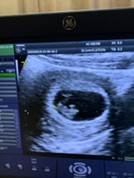

ไปซาวดูมา7สัปดาห์3วันยังไม่เห็นตัวอ่อนค่ะ หมอบอกว่าอาจจะท้องลมกังวลมาก

เราท้อง 7 w ซาวด์หน้าท้องหมอถอนหายใจเลยค่ะ หาตัวน้องไม่เจอ หมอเลยขอซาวด์ผ่านช่องคลอด แล้วก็เจอทั้งตัวน้องและเสียงหัวใจน้องเต้นปกติค่ะ เป็นกำลังใจให้คุณแม่นะคะ ♥️

ของเราตอนที่รู้ว่าท้องใหม่ๆ โทรไปหารพ. ทาง รพ.แนะนำให้รอครบ 9w ค่อยไปซาวค่ะ จะเห็นตัวน้องเลย แล้วก็เห็นเจอน้องเลยค่ะ

มา7w4d พร้อมหัวใจเต้นนะคะ รอสักสัปดาห์ไปซาวด์ใหม่อาจเจอบางทีอาจจะนับวันไข่ตกคลาดคลื่อนนะคะ

ของเรา8w5dจ้าแม่ เห็นเจ้าก้อนตัวน้อยๆ ตอนนี้ได้ 38w1d เงียบกริบไม่มีวี่เเววว่าจะคลอดเลยจ้า

เจอน้องตอน 6 สัปดาห์ค้ะ ใจเยนๆน้ะค้ะ ให้เวลาน้องอีกสักสองสัปดาห์ แม่บางคนใข่ตกใวตกช้า

บ้านนี้7w ก็ยังไม่เห็นค่ะ หมอบอกว่าค่อยมาตรวจใหม่ กลัวท้องลม ตอนนี้แม่27wแล้วค่า 🥰

บ้านนี้ 8w ก็ยังไม่เห็นค่ะ อีก 2 อาทิตย์หมอนัดไปดูใหม่ ก็เห็นค่ะ